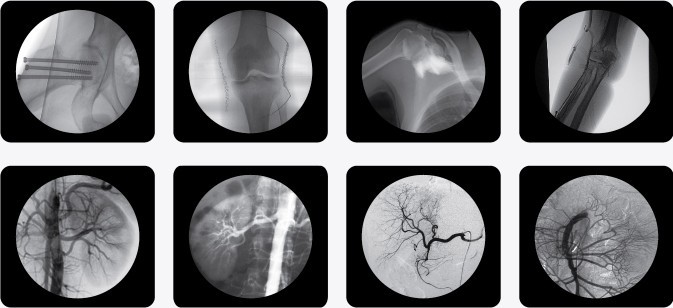

廣泛應用于 介入科、骨科、外科、矯形外科、泌尿外科、脊柱外科、腹部外科、疼痛科、心臟科、消化科、婦科及手術室等。

三、C型臂X光機PLX7000B數字高清影像,支持您做出精確診斷

·全數字化百萬像素影像采集系統,優化設計和配置,為您提供高分辨率、高灰階圖像,支持您做出精確診斷。

·專用高清醫用液晶顯示系統,呈獻給您高亮度、高對比度的臨床圖像;對比自然,有益于診斷的圖像細節顯示更加清晰、層次更加豐富